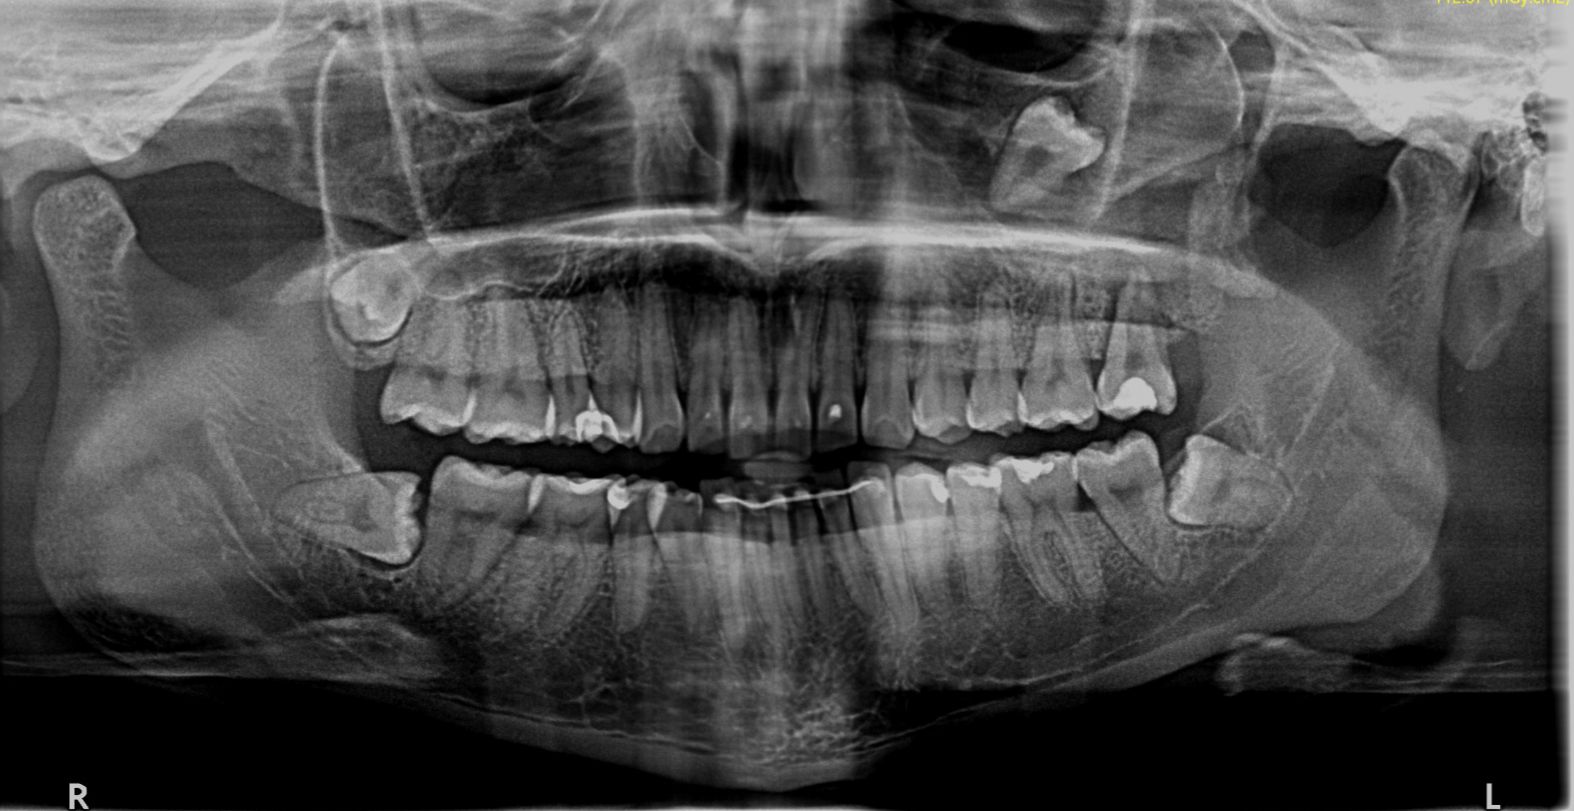

Las muelas del juicio —también conocidas como terceros molares— han causado molestias y extracciones durante décadas. Pero ¿y si la especie humana estuviera en proceso de “perder” estas piezas dentarias? Diversos estudios recientes apuntan a un incremento en la agenesia, es decir, la ausencia congénita del tercer molar. Factores genéticos, dietéticos y evolutivos podrían estar detrás de esta tendencia. En este artículo resumimos la evidencia científica, las posibles causas y las implicaciones para la salud dental y la evolución humana.

La agenesia del tercer molar se refiere a la falta de formación de una o varias muelas del juicio desde el nacimiento. Estudios poblacionales recientes estiman que un porcentaje creciente de personas en todo el mundo carece de uno o más terceros molares. Esta ausencia puede variar según el origen étnico, la genética familiar y las condiciones ambientales durante el desarrollo.

- Estudios poblacionales y revisiones sistemáticas muestran una frecuencia creciente de ausencia de terceros molares en poblaciones modernas comparadas con registros antiguos. Esto apunta a una posible microevolución o cambio adaptativo.

- Investigaciones anatómicas y antropológicas documentan una tendencia a mandíbulas más pequeñas y caras más estrechas en humanos modernos, vinculadas a la dieta y a cambios en el uso de la masticación. Estas modificaciones reducen el espacio disponible para las muelas del juicio.